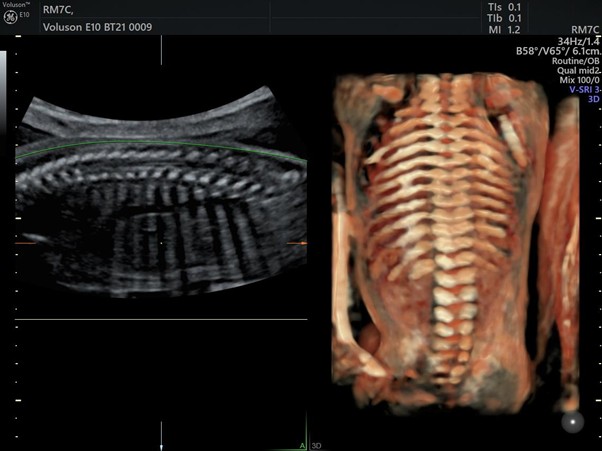

GE Voluson E10

GE Voluson E10 — мировой лидер в области акушерства и гинекологии. Аппарат создан специально для экспертных исследований женского здоровья. Главная особенность — эксклюзивный матричный датчик eM6C, который позволяет получать 4D-изображения с невероятной скоростью и плавностью. Технологии Radiantflow и HDlive придают картинке исключительный реализм и детализацию.

Аппарат УЗИ с поддержкой 4D GE Voluson E10

У Voluson E10 есть 4D-датчик высокого разрешения RIC 6-12-D, позволяющий увидеть мельчайшие детали в первом триместре